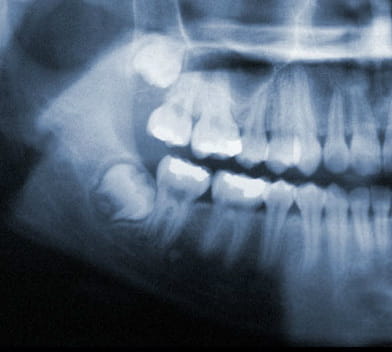

Wisdom teeth also known as third molars are the last teeth to erupt into the mouth. Wisdom teeth typically appear around a person's mid-twenties but can erupt much later. If wisdom teeth don't have enough space symptoms can occur. The wisdom teeth may only partially erupt or might not come through at all. Dentists designate wisdom teeth 'impacted' if they are wholly or partly blocked from eruption into the mouth. The tooth may lie at an angle and remain tipped against an adjacent tooth. Impacted wisdom teeth can cause problems like pain and swelling; The mouth could ache when stretched open wide or it may be difficult to open your mouth. Tenderness when chewing and biting may occur. Earaches may develop from the spread of pain in the mouth. Symptoms may be intermittent but can begin anytime without warning. If you are experiencing symptoms, it is best to get treatment 'usually removal' as soon as you can to avoid potentially expensive and painful complications.